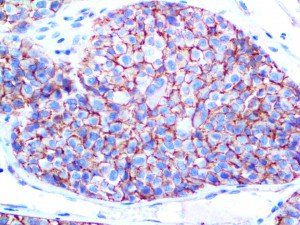

The first cytokines released are interleukin 1β (IL-1β) and tumor necrosis factor-α (TNF-α), which attract a variety of circulating white blood cells (WBCs) to the infection site, including neutrophils, monocytes, macrophages, and natural killer (NK) cells. This response, along with the antipathogenic chemicals released by these cells (i.e., complement), comprise the innate immune response. These cells directly attack the invading pathogen and also release additional cytokines, chief among them interleukin-1 and 6 (IL-6). IL-6 is essential for invoking the adaptive immune response, which calls T-cells, B-cells, and T helper (Th) cells to the infection site. IL-6 also stimulates further recruitment, proliferation and activation of macrophages.

It is the ICU physician who is most likely to witness one of the deadliest manifestations of the abnormal immunological response, the cytokine storm syndrome (CSS). This response is also referred to by some as the cytokine release syndrome (CRS). CSS is characterized by continuous activation and expansion of macrophage and lymphocyte populations, which secrete large amounts of cytokines, causing the cytokine storm. This massive cytokine release is akin to hemophagocytic lymphohistiocytosis (HLH) disease, a syndrome characterized by initial unchecked and persistent activation of cytotoxic T lymphocytes and NK cells.

This activation induces inflammatory monocytes to highly express IL-6, starting a localized and then systemic cascade effect that results in hyperproduction of IL-6, which accelerates the inflammatory process. Because IL-6 also increases vascular permeability, excessive levels cause blood vessels to become very leaky. This, along with clotting factors released from vascular endothelial cells, stimulates the coagulation cascade, resulting in microthrombosis (tiny clots), which leads to ischemia and tissue death of the kidney, intestines, heart, liver, brain and extremities.